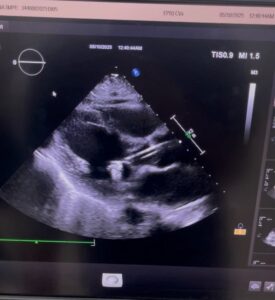

Repeat evaluation revealed a shocking change:

-

LVEF dropped to 15–20% (severe heart failure)

Global left ventricular weakness

Mitral and tricuspid valve leak

Kidney function worsening due to poor blood flow

Using IVUS (Intravascular Ultrasound), the coronary arteries were examined from the inside:

Left main coronary artery area was adequate

Bypass graft was patent

No new critical blockages requiring stents